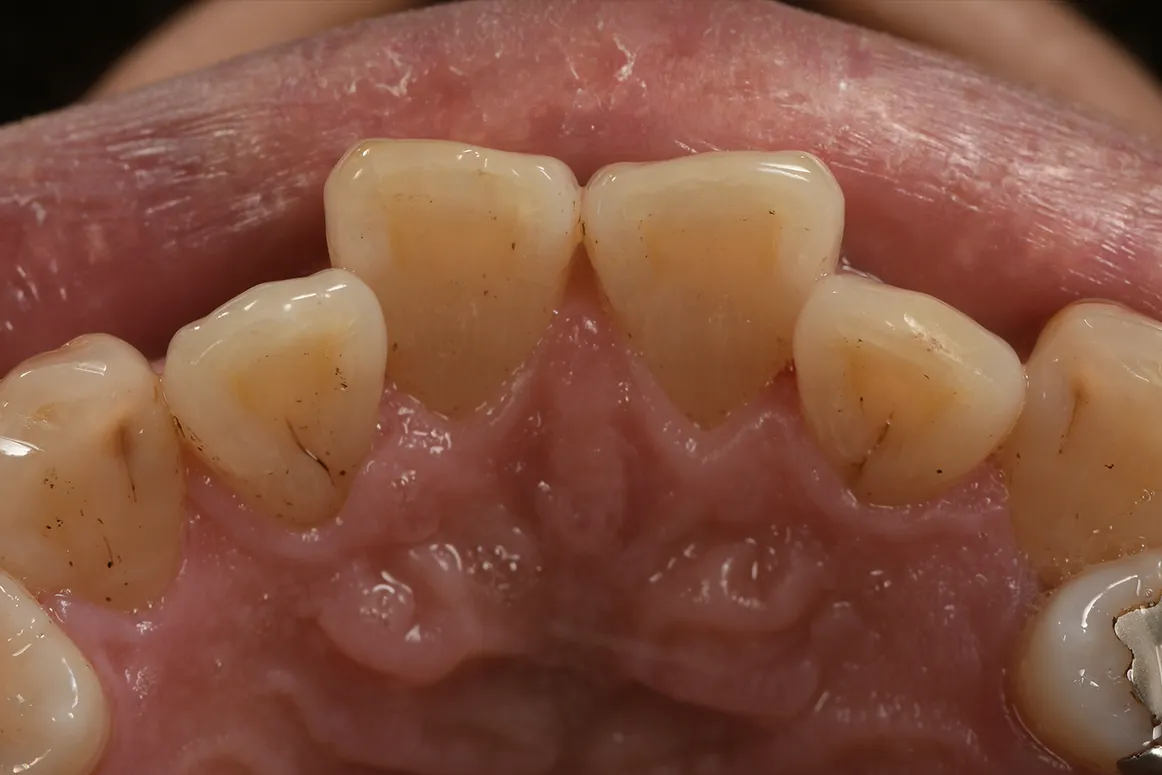

着色汚れが気になり、エアフローで

除去した症例②

主訴

着色汚れが気になる

治療内容

エアフロー